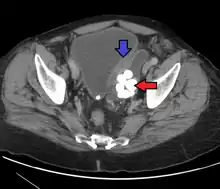

Diagnosis